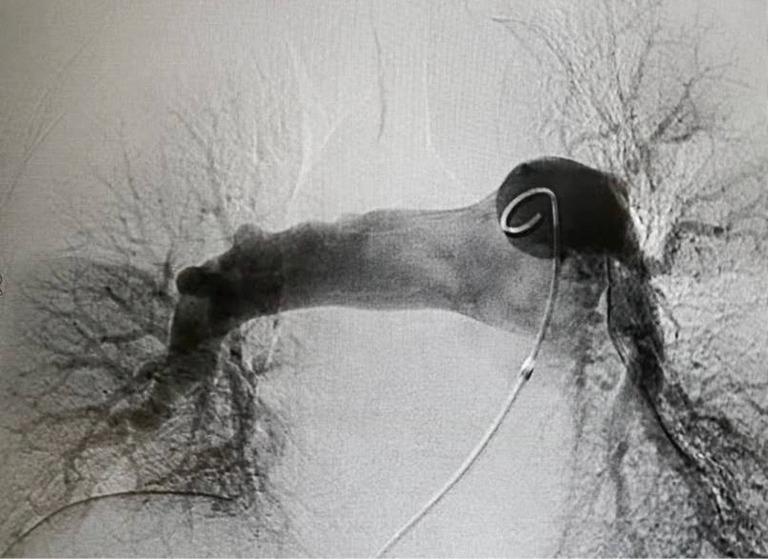

Herein, we report the case of a patient who presented with hypotension and tachycardia accompanied by an asymptomatic right leg deep vein thrombosis, right atrial thrombus, and pulmonary embolus. He had a history of radical resection of colon cancer 1 month prior. And he had developed chest tightness accompanied by stabbing pain in the chest area 1 day ago. He experienced an episode of syncope 8.5 hours ago. So he was referred to the local hospital. After the pulmonary computed tomography angiography (CTA) scan, he was diagnosed with pulmonary embolus and administrated with 5,000 u low molecular weight heparin. Then he was transferred to our hospital. On arrival in the emergency department, the bedside transthoracic echocardiography (TTE) revealed there was an enlarged right atrium and right ventricle, with a floating right atrial mass prolapsing through the tricuspid valve during diastole. The patient accepted anticoagulation treatment, but refused to undergo thrombolysis or surgical embolectomy. Eventually, the right heart thrombi (RiHT) floated to the left main branch of pulmonary artery. It was successfully treated by using AngioJet device and venoarterial extracorporeal membrane oxygenation (VA-ECMO). Our case provides clinical evidence supporting the feasibility and efficacy of AngioJet device and VA-ECMO in the treatment of the RiHT and PE.

在此,我们报告一例患者,其表现为低血压和心动过速,伴有无症状的右下肢深静脉血栓形成、右心房血栓和肺栓塞。他1个月前有结肠癌根治切除术史。1天前出现胸闷并伴有胸部刺痛。8.5小时前发生一次晕厥。因此他被转诊至当地医院。经肺部计算机断层扫描血管造影(CTA)检查后,他被诊断为肺栓塞,并给予5000单位低分子肝素治疗。随后他被转至我院。到达急诊科时,床旁经胸超声心动图(TTE)显示右心房和右心室增大,舒张期有一个漂浮的右心房团块经三尖瓣脱垂。患者接受了抗凝治疗,但拒绝接受溶栓或手术取栓。最终,右心血栓(RiHT)漂浮至肺动脉左主支。使用AngioJet装置和静脉 - 动脉体外膜肺氧合(VA - ECMO)成功对其进行了治疗。我们的病例提供了临床证据,支持AngioJet装置和VA - ECMO治疗RiHT和PE的可行性和有效性。